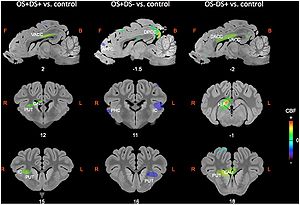

- 4.18 Microstructural Changes in the Striatum and Their Impact on Motor and Neuropsychological Performance in Patients with Multiple Sclerosis

The regions-of-interest (ROIs) were manually drawn by an experienced radiologist by using the b 1000 images, averaged for all measured directions, the FA maps and the proton-density weighted images. For that purpose, the maps of ADC, FA, R2 and R2* as well as the proton-density weighted images were first co-registered. The ROIs were segmented by syncing the b 1000 images, averaged for all measured directions, the FA maps and the proton-density weighted images in ImageJ. The ROIs were stored in the ROI manager and transferred to the co-registered maps. The segmented brain regions were highlighted in different colors: CN—black; PU—red; GP—green; TH—white; SN—blue; CC—cyan. The diffusion-weighted images, the R2 and R2*-weighted maps were transferred to the 3D Slicer software in order to co-register the R2 and the R2* maps as well as the MD and the FA maps |